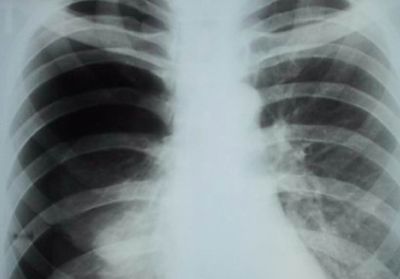

- рентгенография органов грудной клетки;

- рентгенографию;

- рентгенографии грудной клетки;

- Боль в спине справа бывает из-за пневмонии правосторонней. В этом случае ее интенсивность напрямую зависит от стадии болезни. Дополнительно всегда возникают присущие воспалению симптомы, которые и позволяют определить ее – это хрипы, температура и др.